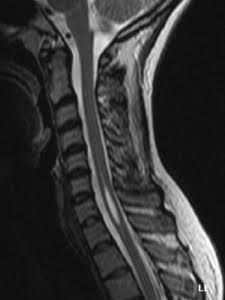

Syringomyelia is a disorder in which a fluid-filled cyst (called a syrinx) forms within the spinal cord. Over time, the syrinx can get bigger and can damage the spinal cord and compress and injure the nerve fibers that carry information to the brain and from the brain to the rest of the body.